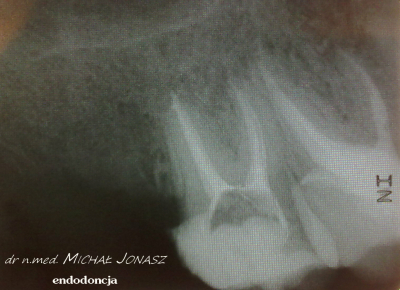

Portfolio Umawianie wizyt Cennik Kontakt Galeria Endodoncja - Leczenie kanałowe Implantologia Protetyka Ortodoncja Higienizacja Wybielanie Stomatologia Zachowawcza Periodontologia Umawianie wizyt Cennik Kontakt Galeria